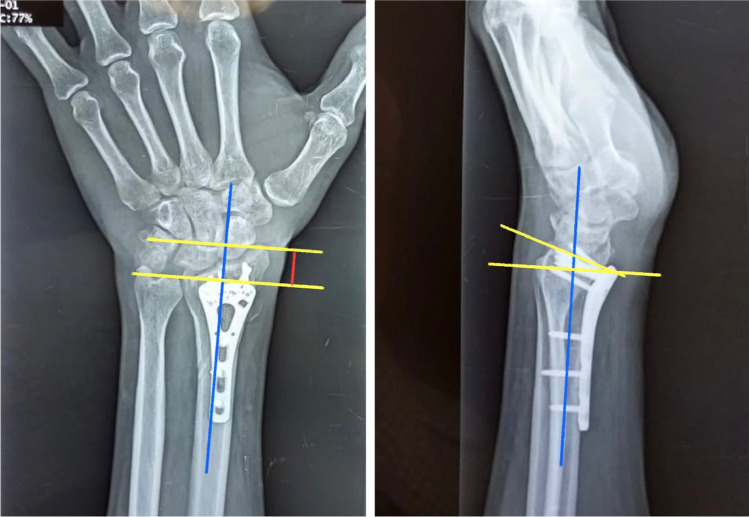

Several authors described flexor tendon complications following volar plating of distal radius fractures. This occurred as a late event in 4.3% of patients according to Soong et al. series. Fifty percent of the reported cases in the literature occurred within six to 26 months after the operation due to irritation (flexor tenosynovitis) with subsequent partial or complete rupture [24–26].

In our series, there were two patients with flexor tendon rupture. The first one had the flexor digitorum profundus (FDP) index ruptured at 11 months post-operatively, and this was related to a prominent proximal screw that was misplaced in an incomplete locking mode with about 2 mm prominence beyond the locking hole. The patient had a successful tendon transfer (extensor carpi radialis longus (ECRL) to FDP). The second patient developed flexor pollicis longus (FPL) rupture 26 months post-operatively (Fig. 6). The plate was prominent distal to the watershed line (Soong type 2). The patient had a successful tendon transfer (flexor digitorum superficialis of the ring finger (FDS-IV) to the distal stump of FPL).

Fig. 6.

A case with frayed FPL tendon due to repeated friction with a plate which was placed distal to the watershed line

These two cases did not add to our judgment about which volar locking system related to tendon rupture, as both of them (especially the first one) are related to a technical error that is totally avoidable. The attritional rupture of FPL (like the second case) may add to the fact that fixed angle plate is less forgiving when it comes to malposition.